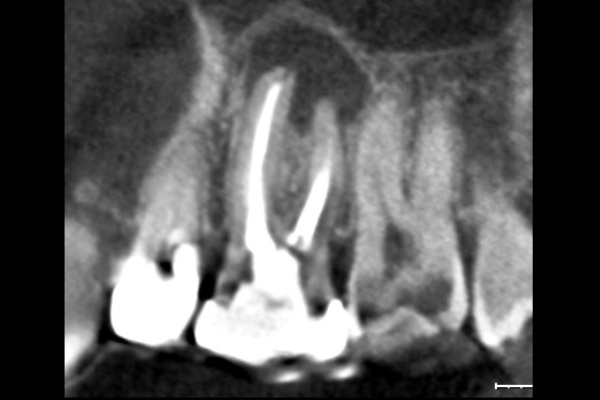

30代男性の前歯部の症例

- 「咬んだら痛い」とのことでご来院されました。数週間前から症状があり、他の医院では「抜歯の可能性がある」と言われ、不安に感じていらっしゃいました。

3.病巣の摘出と歯根端の切除

マイクロスコープ(歯科用顕微鏡)で術野を拡大し、膿の袋をきれいに取り除きます。その後、細菌の温床となっている根の先端を約3mm切除します。

4.根管の封鎖(逆根管充填)